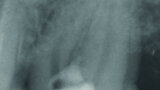

Fig. 5 : Radiographie de la fermeture de la perforation après la première visite.